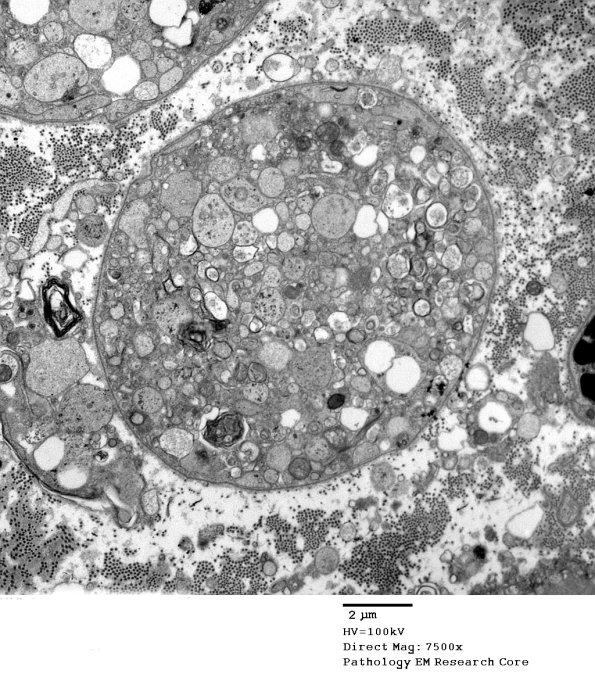

2C3,4 In this degenerating axon there are fragments that may be axon derived.